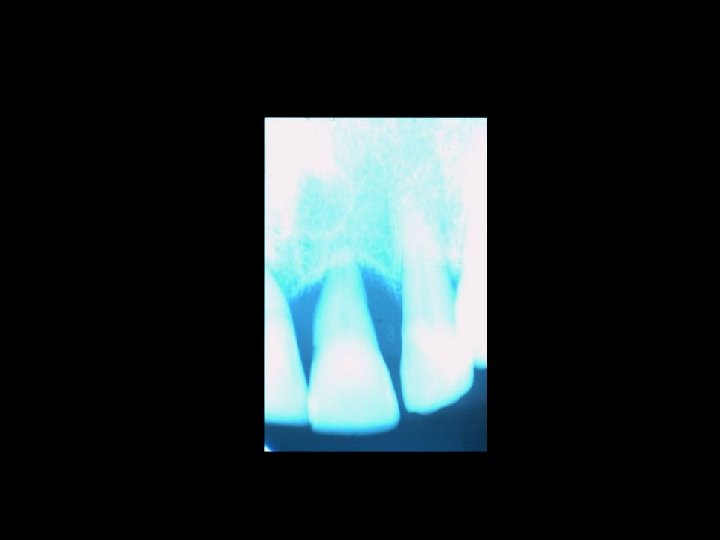

Responsabilità professionale dell’Odontoiatra La diagnosi Ø Messa in atto di interventi conosciuti e di provata esperienza Ø Atti ed omissioni Ø Nesso tra danno e intervento Ø

Il contenzioso PRINCIPALI AMBITI Ø Ø Ø La diagnosi La chirurgia orale La terapia conservativa Il trattamento delle anomalie dento-scheletriche La riabilitazione protesica